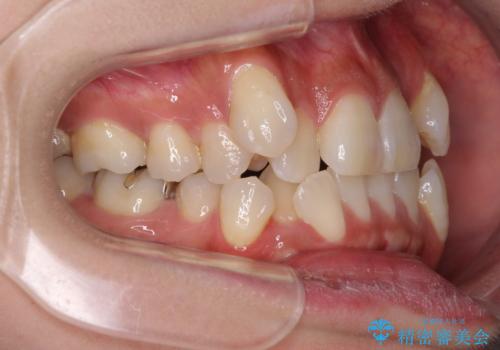

- 八重歯や前歯のデコボコを気にして来院された患者様です。

目立たない装置を希望されたので、上顎が裏側装置のハーフリンガルを選択し、上下左右の小臼歯(計4歯)を抜歯して矯正治療を行うこととしました。

補助装置を併用することで、八重歯を速やかに改善し、治療期間の短縮を図ることとしました。